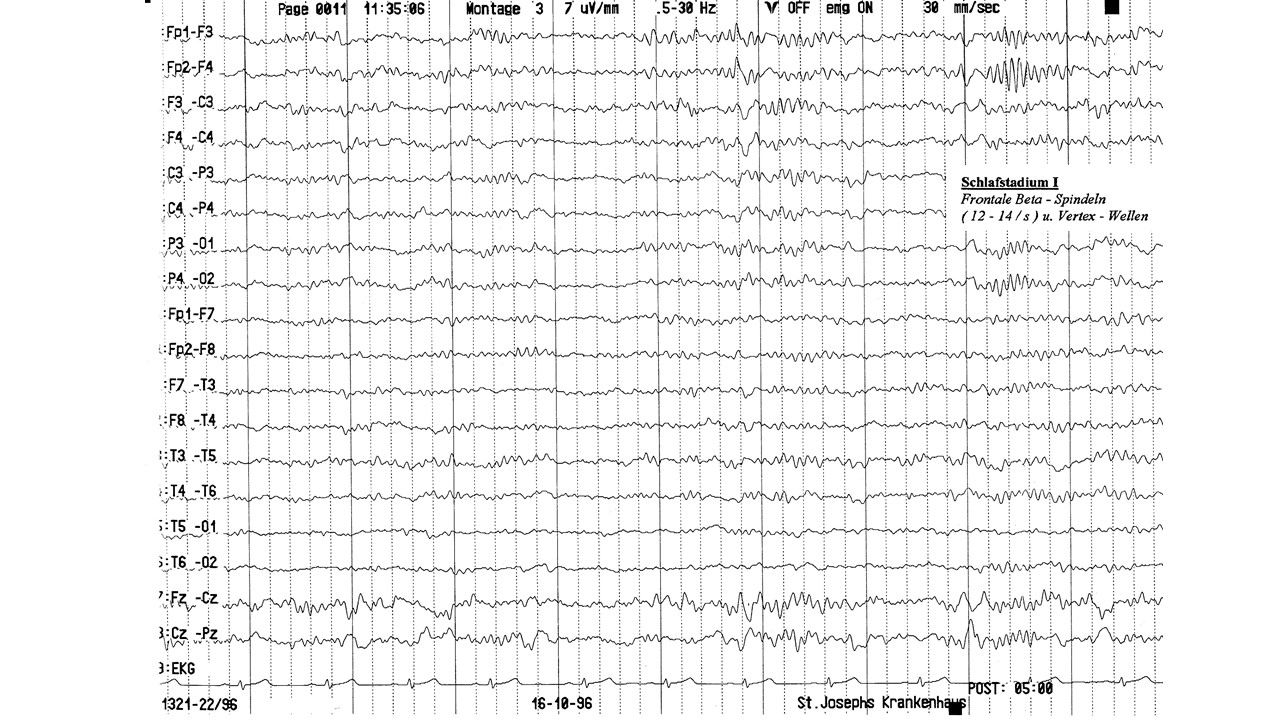

folie93.jpg